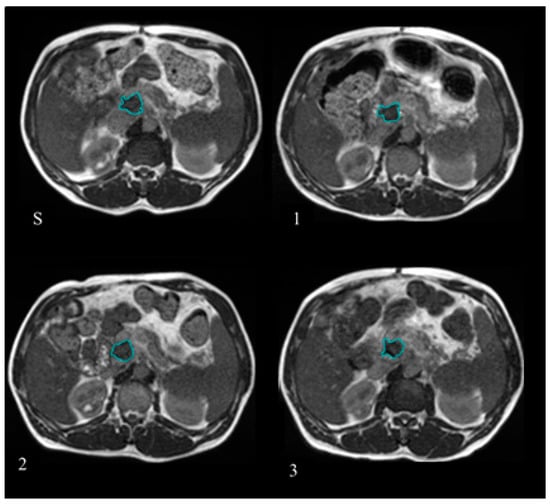

GTV delineation was retrospectively checked for anatomical consistency on the MR images selected for the analysis using the MIM software (version 6.7.6 MIM Software Inc., Cleveland, OH, USA) by two radiation oncologist experts in the gastrointestinal malignancies. Figure 1 reports the example of one patient where the GTV was delineated at simulation and at the treatment fractions selected to have BED levels of 20, 40, and 60 Gy.

Figure 1. Gross tumour volume (GTV) delineated at the treatment simulation (S) and at the different treatment fractions selected for the Delta Radiomics analysis, corresponding to BED levels of 20 Gy (1), 40 Gy (2), and 60 Gy (3). The GTV contours are reported in blue lines